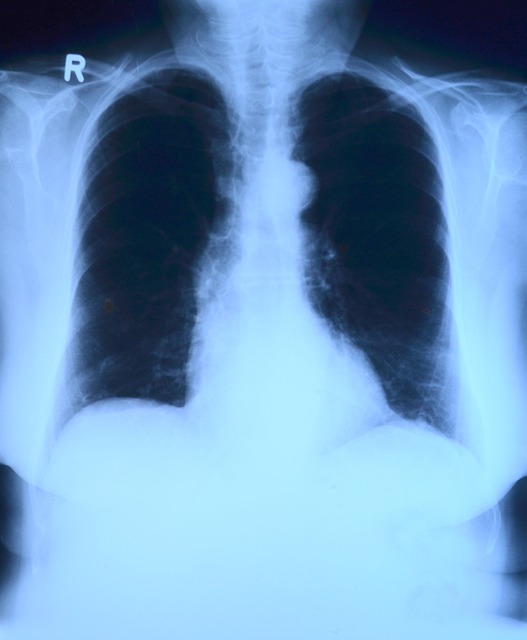

- 흉부 X선: 폐렴이 진행된 경우 폐의 염증 상태를 확인할 수 있습니다.